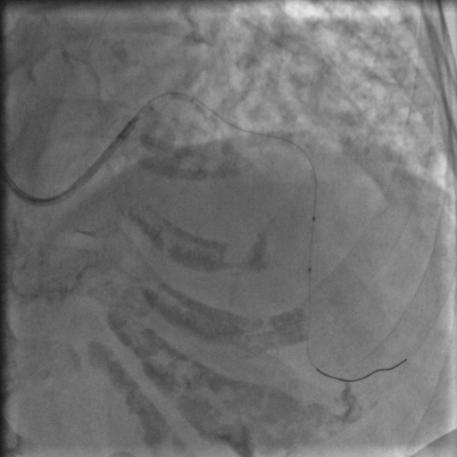

按照常规,更换指引导管,送入导丝,顺利通过闭塞病变到达前降支远端,很顺利,D-to-B时间70分钟,达标,曙光在前头。

图5

导丝过了之后常规造个影:

图6

没通,这个也很正常,急性冠脉闭塞导丝过了之后血栓还堵着是很经常的事,按常规打点欣维宁,考虑到她86岁,打入8ml欣维宁,造影: